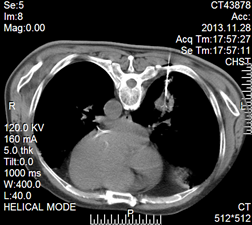

手术中CT引导图片

CT扫描提示右侧周围型肺癌

该患者因长期吸烟,反复咳嗽,通过病理确诊为右侧周围型肺癌,考虑到患者年龄大,长期患高血压糖尿病,同时合并肾功能不全,承受不住手术风险及术后化疗,因此转入我院微创介入科施行CT引导下肺癌射频消融治疗术。